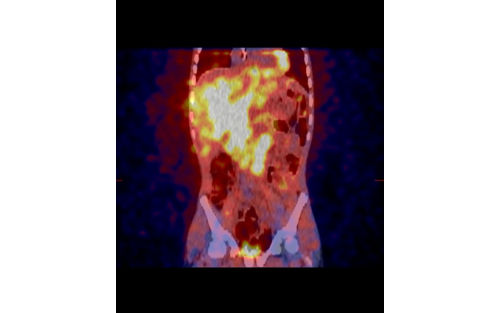

Neuroblastoma often starts in the abdomen, either in the adrenal gland or in other nerve cells. It can also form in the neck, chest, or pelvis.

• Imaging tests to learn about the size and location of the tumor(s)